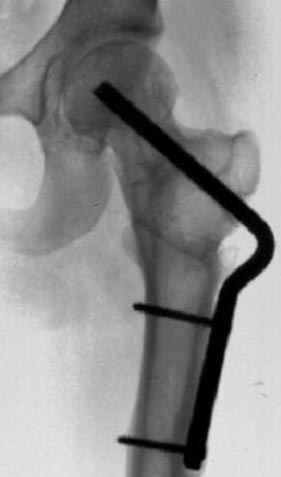

На рисунке N1 предоперационный план лечения ложного сустава шейки бедра- линия ложного сустава, угол и направление введения импланта, клиновидная остеотомия в градусах и миллиметрах, второй снимок после коррекции, расчет, на сколько удлиняется конечность и размеры импланта;

N3 рисунок окончательный снимок, после операции моя рентгенограмма должен выглядеть примерно как эта картина. На N4 снимке клин перед удалением; N5 послеоперации 3 нед.; N6 окончательная рентгенограмма.

варус при проксимальном отделе 95 градусной пластиной.